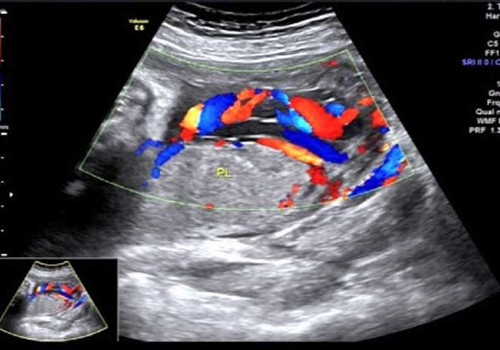

2017年7月10日上午就是在這間小黑屋里,一名34周孕婦正在進行產科常規超聲檢查,當探查到胎盤時,朱新娟醫師一臉凝重,她發現了異常!經科主任吳建軍、副主任醫師趙瑩會診,發現該孕婦腹中胎兒臍帶走形異常、并異常插入胎盤,沿胎膜走行約5.2cm后才進入胎盤實質,且血管聚集成堆于宮頸內口處,考慮臍帶帆狀插入胎盤并血管前置。此現象是非常少見的產科急癥!極易造成血管斷裂!大出血!造成胎兒死亡!而這一切,產婦和家屬卻全然不知。情況緊急,朱新娟立即電話報告產科危急值!

聲像圖示:臍帶帆狀插入胎盤并血管前置

產科接到危急值報告后,即刻將該孕婦收治入院,給予密切監護、治療,并于7月20日上午9:40,為該孕婦行剖宮產,娩出一名2000g女嬰,母女平安!數十分鐘后胎盤娩出,確系少見的臍帶帆狀插入胎盤并血管前置!產科馬主任激動地拉著吳主任的手說:“你們超聲醫生太棒啦!你們就是我們產科醫生的眼睛!不但救了這對母女,也‘救’了我們產科醫生啊!”